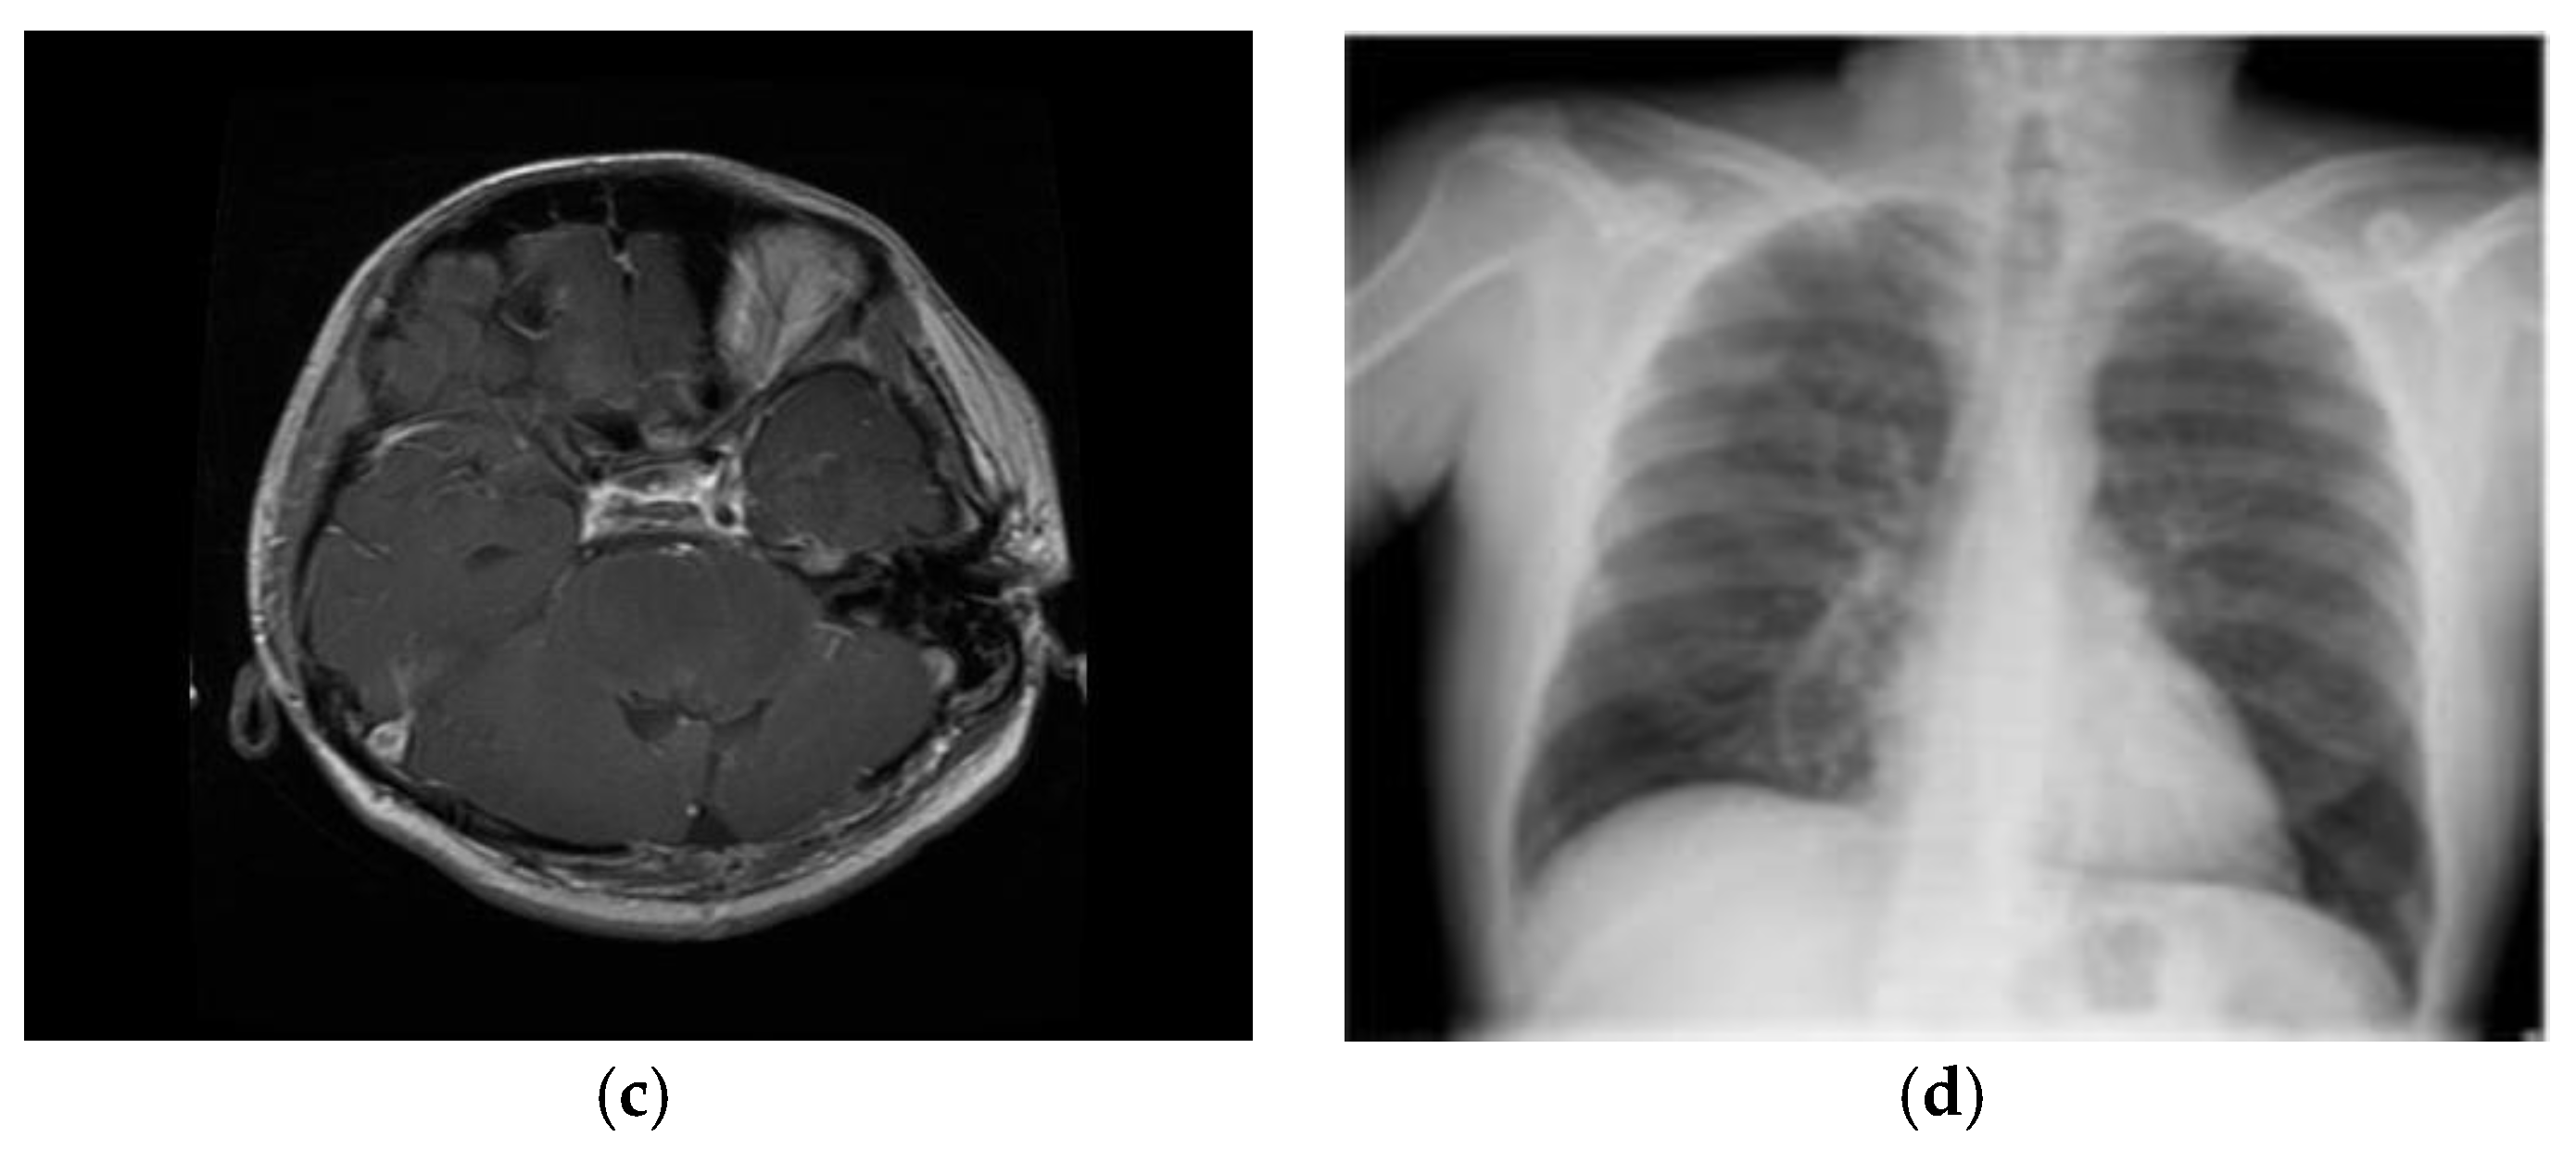

| Images | Lightweight cryptography algorithms | NPCR | UACI | Cross entropy |

|---|---|---|---|---|

| ECG | CTE + Dynamic Chaotic [31] | 99.623 | 47.168 | 0.139 |

| ASCONv1.2 + HOC + MWG | 99.700 | 48.500 | 13.950 | |

| EEG | CTE + Dynamic Chaotic [31] | 99.625 | 44.325 | 0.110 |

| ASCONv1.2 + HOC + MWG | 99.710 | 45.800 | 12.120 | |

| MRI | CTE + Dynamic Chaotic [31] | 99.614 | 39.678 | 0.134 |

| ASCONv1.2 + HOC + MWG | 99.690 | 41.000 | 13.545 | |

| X-Ray | CTE + Dynamic Chaotic [31] | 99.617 | 31.225 | 0.132 |

| ASCONv1.2 + HOC + MWG | 99.695 | 33.000 | 13.340 |